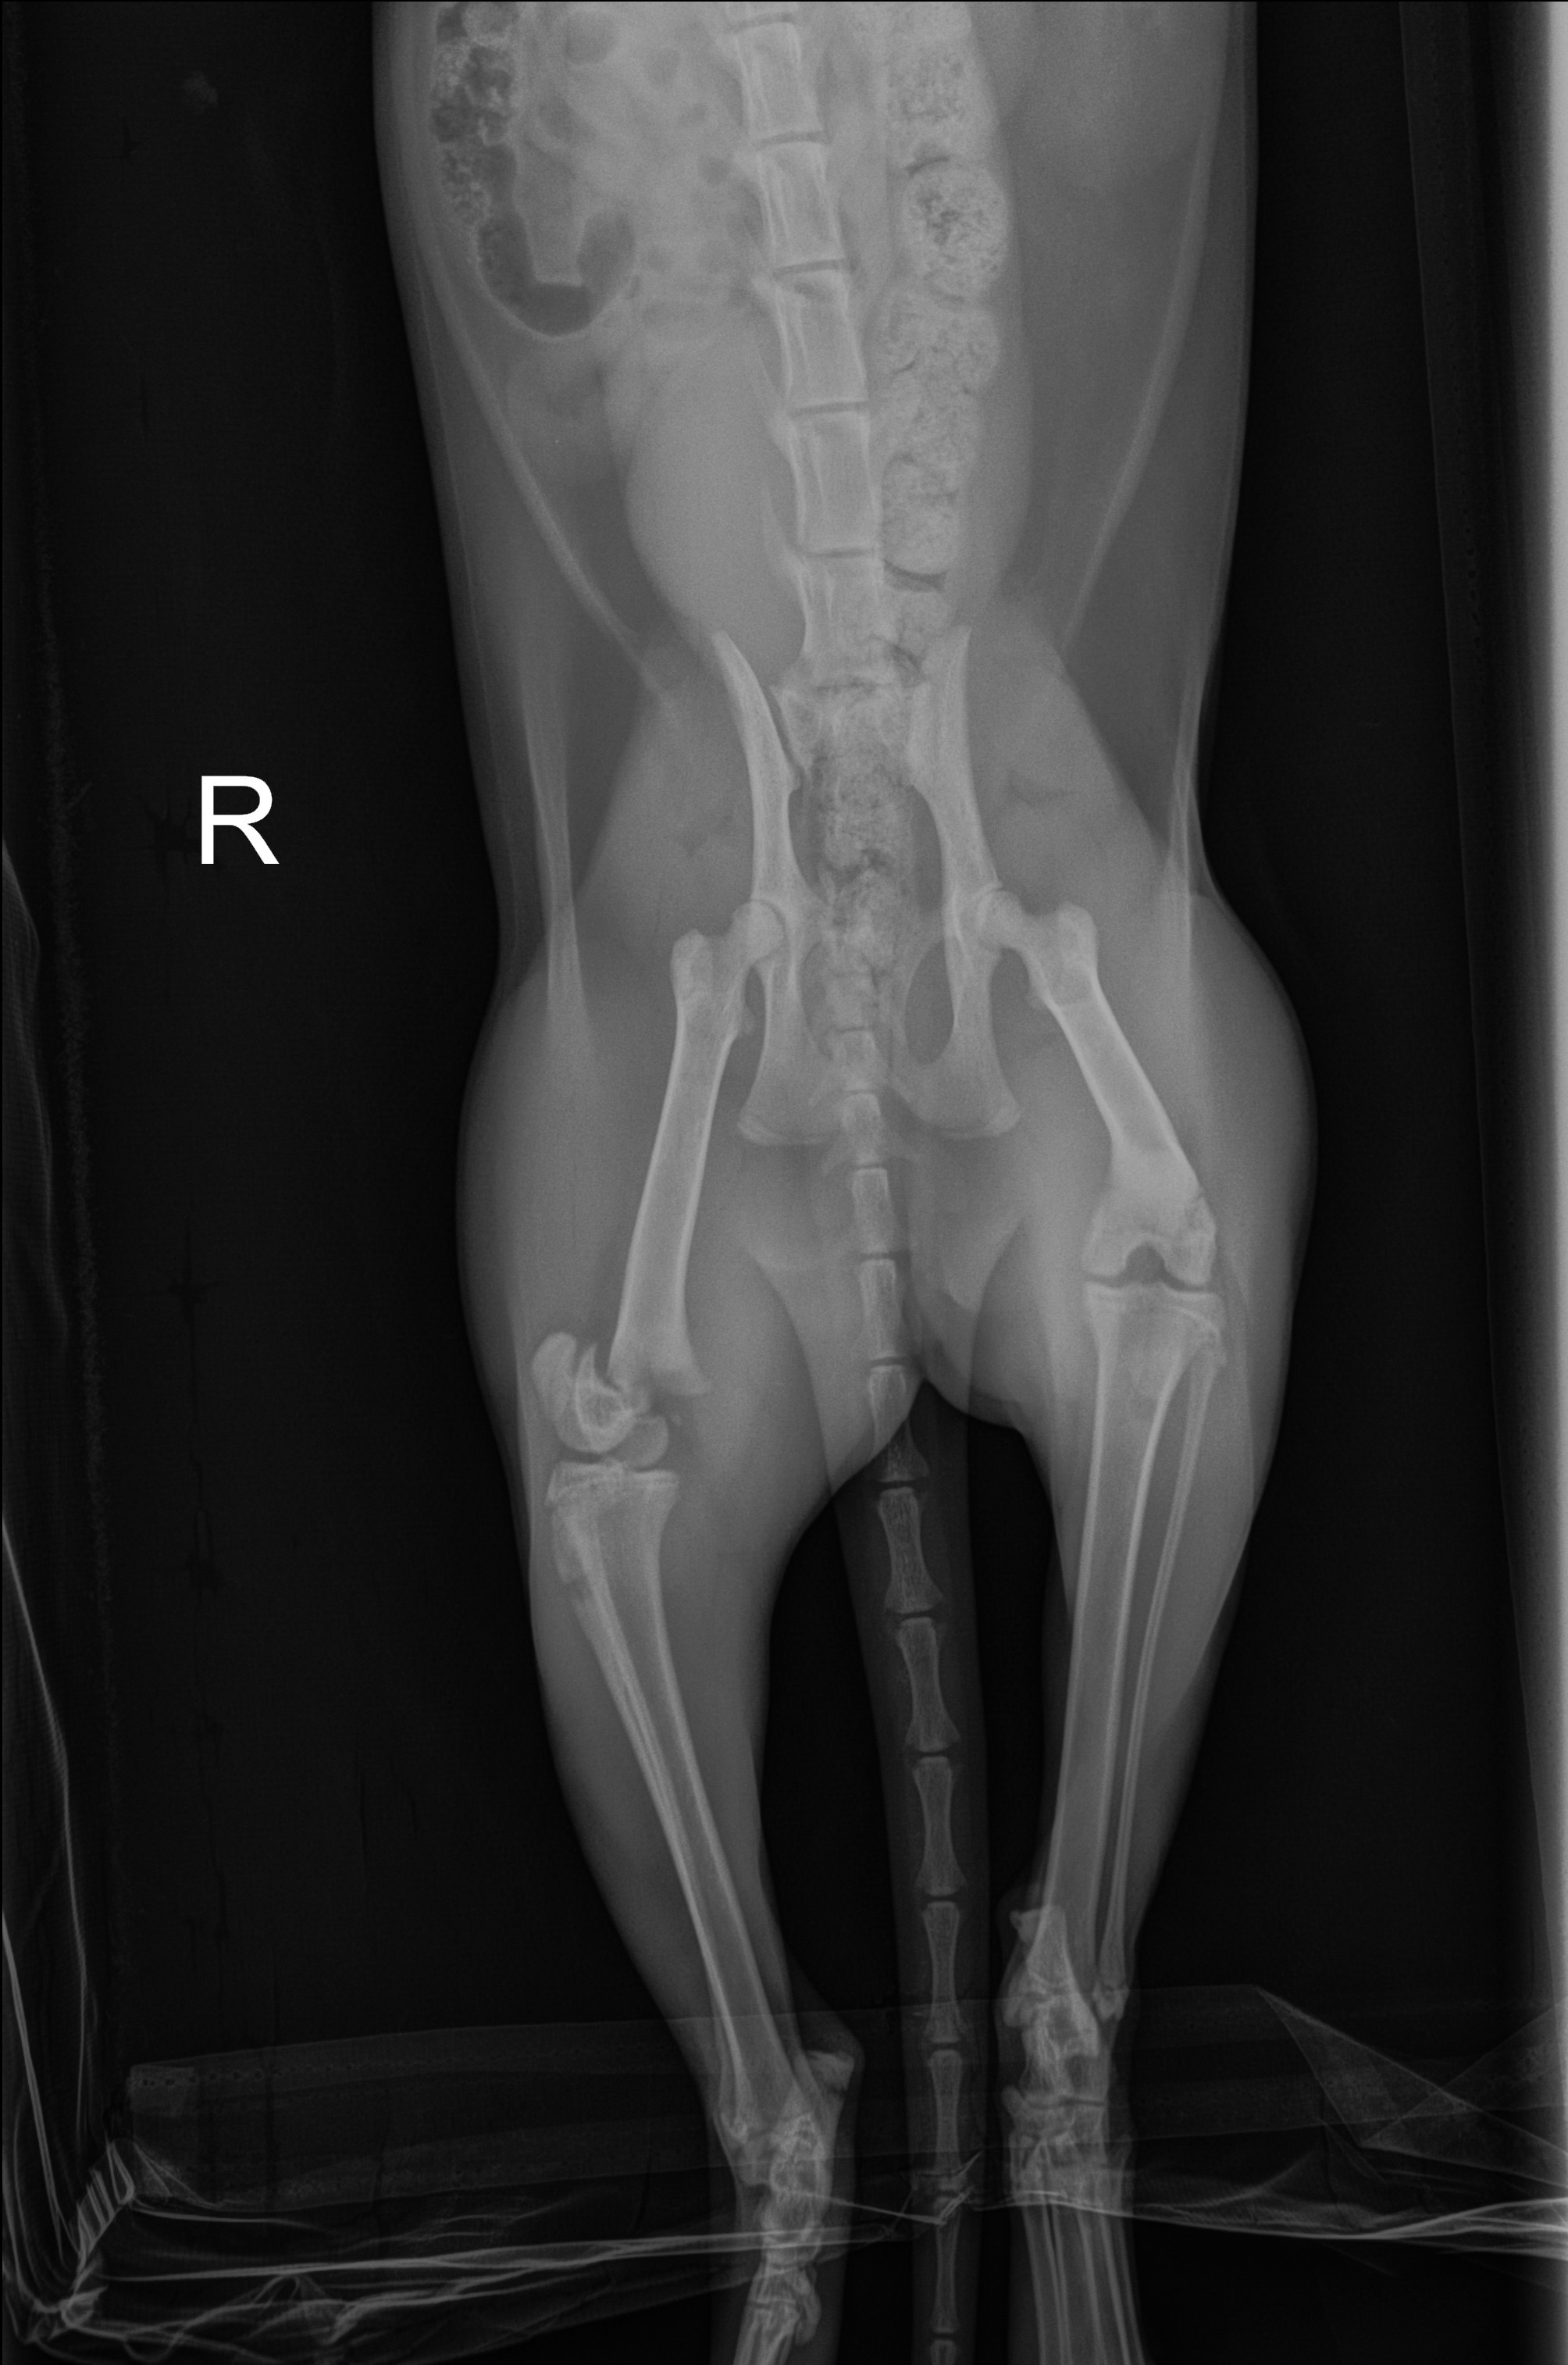

Today, my second cat, Jiji, broke her right leg. I have already spent $600 on x-rays and the initial exam. Orthopedic surgery is now required to set the fracture and install pins to hold the bone in place. I have not received an estimate for how much this procedure will cost.